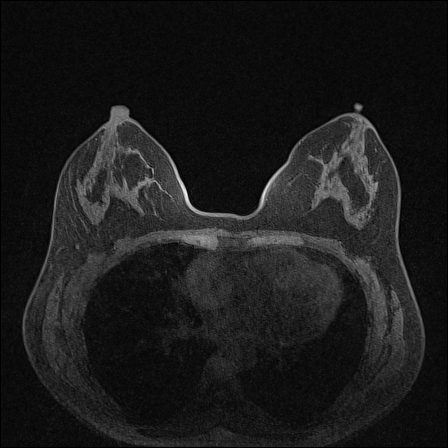

Magnetic field strength. 3T scanners offer higher magnetic field strength, improving signal-to-noise ratio (SNR) and image resolution for sharper, more detailed images [24]. However, they are more prone to artifacts, heating effects, and signal loss, especially around metal implants [5]. As such, our proposed dataset involving this spurious signal features a non-local spurious signal that influences the entire image rather than a localized region. An example set of images obtained from 1.5T and 3T devices are provided in Figure 3, showing that it is visually not possible to distinguish 1.5T MRIs from the 3T ones.